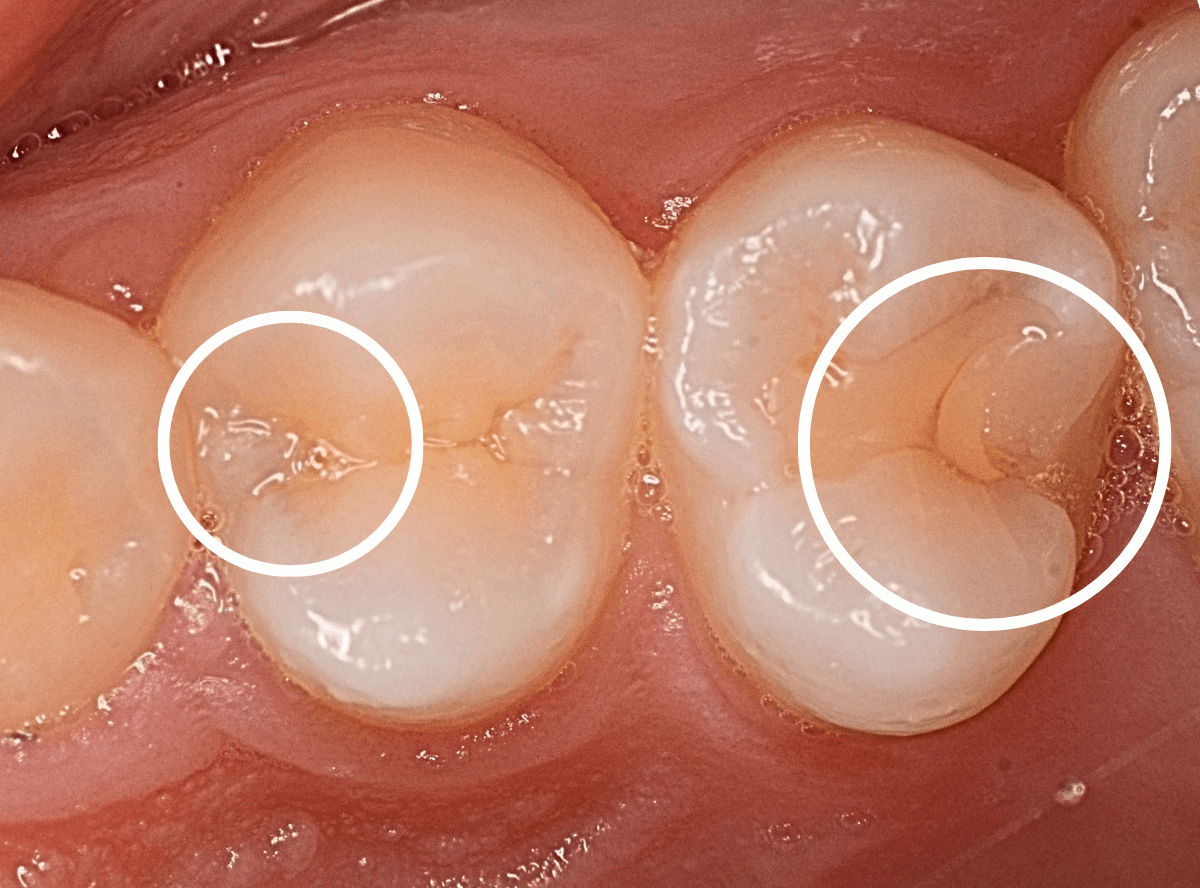

Case.13 問題なさそうなレジンの下で深い虫歯

他の歯の治療希望で来院された患者さんで、レントゲンで大きな虫歯が見つかった方です。

以前に虫歯を削って、レジンをつめる治療がしてあります。

表面を見る限り、特に問題はなさそうです。

まずは、麻酔をしてつめ物を慎重に外してみます。

両歯とも、色々嫌な予感のする所見です。

レジンを除去して虫歯を調べます。

赤い部分が虫歯です。

少しずつ虫歯が出てきました。

慎重にレジンを外して、全ての虫歯を除去しました。

レントゲンから予想される通り、かなり大きな虫歯でした。

症状が出る前に治療が出来て良かったです。